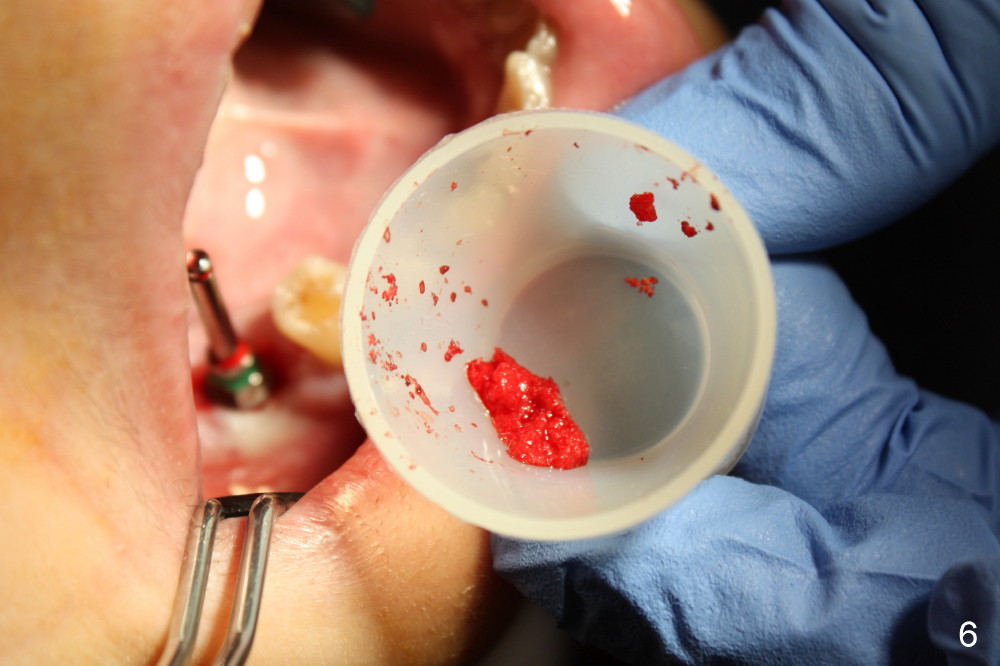

The socket of #30 heals one month after extraction (Fig.1 *). What is unexpected is that the alveolus has started to shrink (follows arrowheads). It is also unexpectedly easy to tap in RT2 (flapless). With insertion of a 2.0 mm pilot drill, PA reveals that osteotomy is not inside the septum (Fig.2 S). Redirecting osteotomy with the same pilot drill leads to insertion into the septum, but the upper end of the pilot drill should be moved mesially in next steps (arrow). With that and treatment plan in mind, combination of osteotomes, Bicon reamers and taps results in right trajectory (Fig.4 * (5x20 tapered tap), Fig.5 (6x17 tapered tap)). Harvested bone (Fig.6) is transferred to the mesial socket and condensed (Fig.7). Insertion torque of 6x17 mm implant is more than 60 Ncm. The lower end of the implant remains in the center of the septum (Fig.8 <). The gingiva contacts the implant tightly (Fig.9, 10) except mesiobucally (Fig.9 <). Periodontal dressing is used to protect the wound (Fig.11,12).